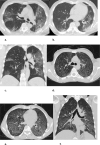

Background Clinicians need to rapidly and reliably diagnose coronavirus disease 2019 (COVID-19) for proper risk stratification, isolation strategies, and treatment decisions. Purpose To assess the real-life performance of radiologist emergency department chest CT interpretation for diagnosing COVID-19 during the acute phase of the pandemic, using the COVID-19 Reporting and Data System (CO-RADS). Materials and Methods This retrospective multicenter study included consecutive patients who presented to emergency departments in six medical centers between March and April 2020 with moderate to severe upper respiratory symptoms suspicious for COVID-19. As part of clinical practice, chest CT scans were obtained for primary work-up and scored using the five-point CO-RADS scheme for suspicion of COVID-19. CT was compared with severe acute respiratory syndrome coronavirus 2 reverse-transcription polymerase chain reaction (RT-PCR) assay and a clinical reference standard established by a multidisciplinary group of clinicians based on RT-PCR, COVID-19 contact history, oxygen therapy, timing of RT-PCR testing, and likely alternative diagnosis. Performance of CT was estimated using area under the receiver operating characteristic curve (AUC) analysis and diagnostic odds ratios against both reference standards. Subgroup analysis was performed on the basis of symptom duration grouped presentations of less than 48 hours, 48 hours through 7 days, and more than 7 days. Results A total of 1070 patients (median age, 66 years; interquartile range, 54-75 years; 626 men) were included, of whom 536 (50%) had a positive RT-PCR result and 137 (13%) of whom were considered to have a possible or probable COVID-19 diagnosis based on the clinical reference standard. Chest CT yielded an AUC of 0.87 (95% CI: 0.84, 0.89) compared with RT-PCR and 0.87 (95% CI: 0.85, 0.89) compared with the clinical reference standard. A CO-RADS score of 4 or greater yielded an odds ratio of 25.9 (95% CI: 18.7, 35.9) for a COVID-19 diagnosis with RT-PCR and an odds ratio of 30.6 (95% CI: 21.1, 44.4) with the clinical reference standard. For symptom duration of less than 48 hours, the AUC fell to 0.71 (95% CI: 0.62, 0.80; P < .001). Conclusion Chest CT analysis using the coronavirus disease 2019 (COVID-19) Reporting and Data System enables rapid and reliable diagnosis of COVID-19, particularly when symptom duration is greater than 48 hours. © RSNA, 2020 Online supplemental material is available for this article. See also the editorial by Elicker in this issue.

Figures